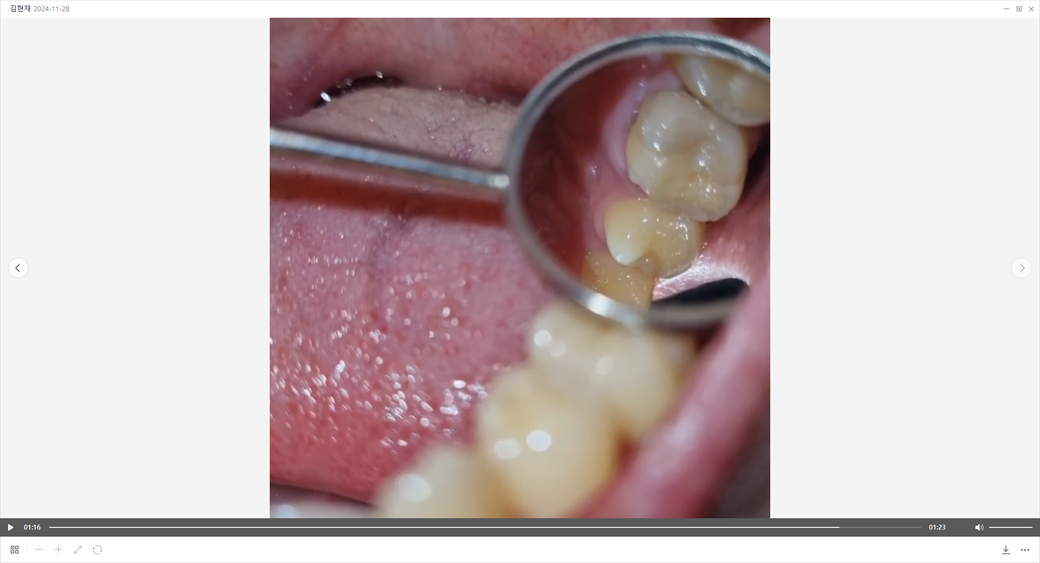

이빨 부분이 검은색이고 잇몸 부분에 살짝 틈이 있는데 충치인가요?

중간 이빨 부분만 살짝 색갈이 검은색이고 뭔가 느낌이 없고 살짝 피맛이 나는 것 같아서 올려봤습니다.

그리고 잇몸 부분에 보니까 살짝 틈이 있더군요. 뭔가 크게 문제가 있을까요?

덴탈미러를 가지고 사진을 잘 찍으셨네요.

치아와 치아 사이에 틈이 생기면 음식물이 껴서 잇몸이 붓거나 피가 날 수 있습니다.

또한 치아가 썩게 되면 검게 보이기도 하고요.

간단한 엑스레이를 찍어서 진단을 정확히 하고 그에 맞는 적절한 치료를 받으시면 될 것 같습니다.